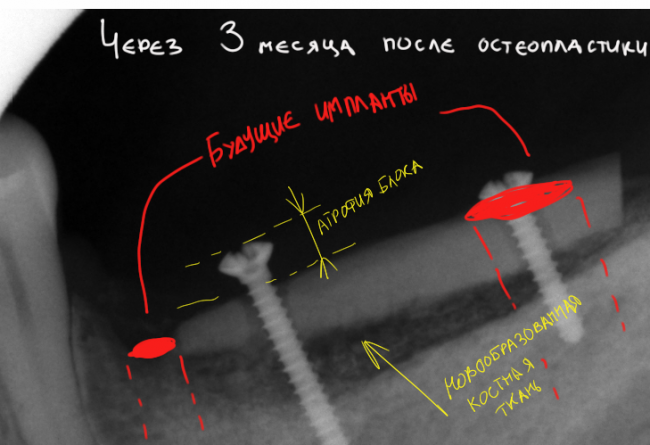

4. Через три месяца — подготовка к имплантации.

Мы приступаем к имплантации через три месяца. Некоторые доктора называют срок в 5-6 месяцев после остеопластики, но, на мой взгляд, это слишком долго.

Во-первых, достаточная для имплантации интеграция блока происходит вообще за 2-2,5 месяца.

Во-вторых, не забывайте про то, что пересаженные костные блоки также склонны к атрофии.

Это можно увидеть по прицельному снимку, который мы сделали через 3 месяца после остеопластики:

Вспомните, как стояли винты сразу после операции и как они выглядят сейчас.

Обратите внимание на появление новообразованной костной ткани под блоком — на снимке наглядно прослеживается ее губчатая структура. Пока границы слоев костной ткани видны хорошо, но, в дальнейшем, они почти исчезнут.

Пациентка озвучила свое решение по поводу количества имплантов — мы решили установить пока два импланта в область 35, 37 зубов, сделать на них мостовидный протез. Если вдруг по каким-то причинам он ее не устроит — мы всегда можем доставить имплантат 36 зуба и сделать три одиночные коронки. Без проблем — костной ткани теперь достаточно.

В данной работе я использовал импланты Friadent Xive. Это наш с пациенткой выбор.